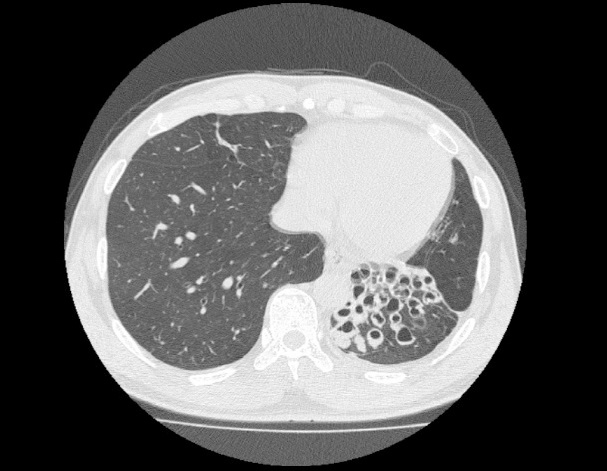

기관지확장증의 CT 사진